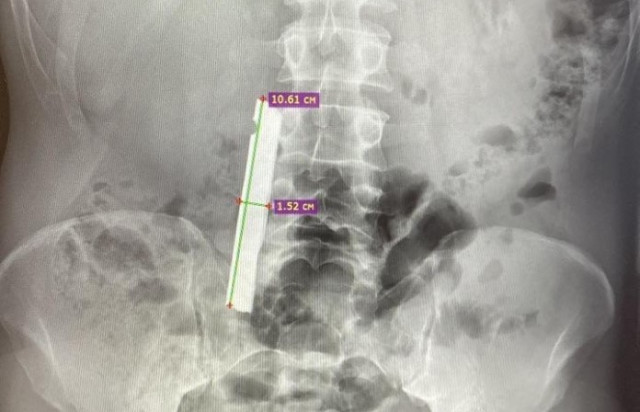

В Советской районной больнице (ХМАО) врачи помогли мужчине, в двенадцатиперстной кишке которого обнаружили инородное металлическое тело. Об этом сообщили в окружном департаменте здравоохранения.

Инородный предмет обнаружили благодаря эзофагогастродуоденоскопии. Сначала врачам удалось переместить предмет в желудок, но дальнейшая попытка извлечения не увенчалась успехом.

– В связи с этим было принято решение о проведении вмешательства под наркозом. Дежурный анестезиолог Александр Кобзев в экстренном порядке ввёл пациента в состояние наркоза. Эндоскопическое вмешательство в таких условиях завершилось успешно — инородное тело было извлечено, – говорится в сообщении.

Послеоперационный осмотр не выявил повреждений внутренних органов. Как предмет попал в тело пациента, не уточняется.